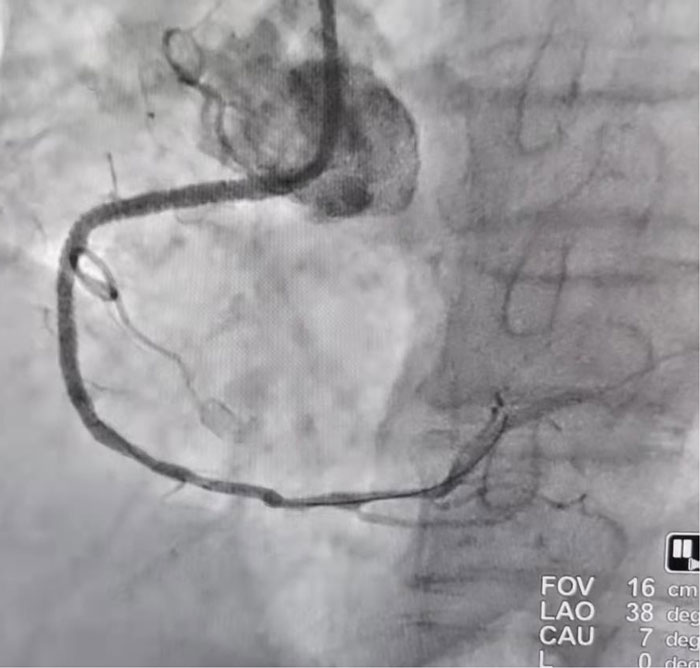

患者冠狀動(dòng)脈造影結(jié)果顯示:前降支中段60%-70%節(jié)段性狹窄,第二對(duì)角支開口至近端60%節(jié)段性狹窄;回旋支(細(xì)?。┲卸?0%局限性狹窄;右冠狀動(dòng)脈近端100%閉塞。向家屬告知病情后,決定干預(yù)右冠狀動(dòng)脈。

(術(shù)前右冠狀動(dòng)脈影像)